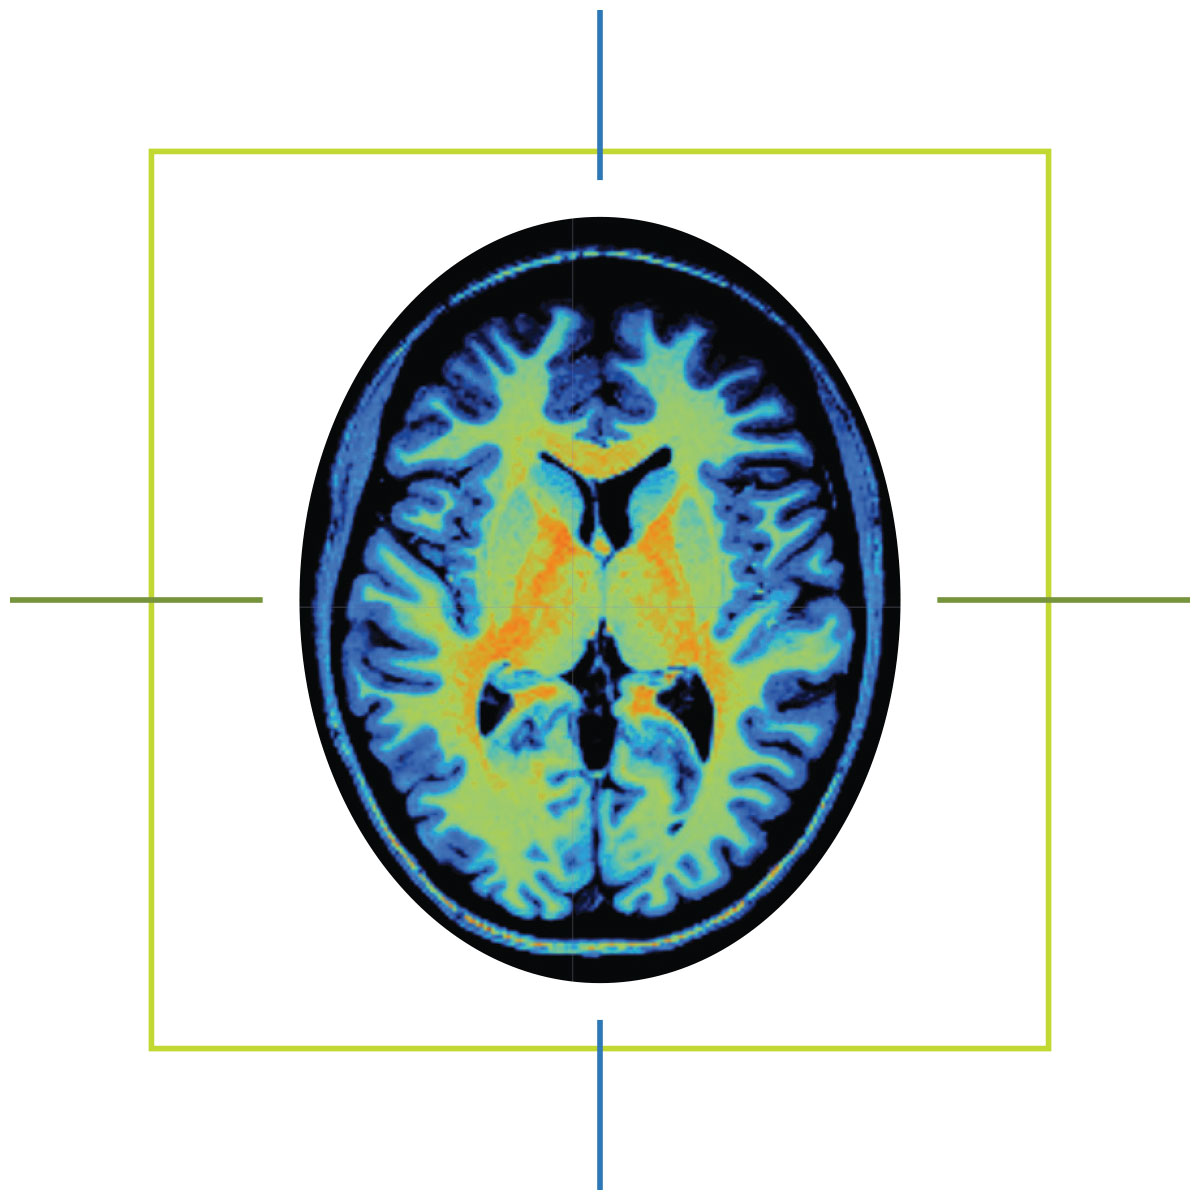

The McCausland Imaging Center boasts an MRI twice the strength of typical MRIs

He also knew his speech would never return to how it was before the stroke. But after seeing the scan of his brain — the dark hole of necrotic tissue on one side, the vibrant patchwork of healthy tissue on the other — the man who spent 30 years as a mechanic and quality control supervisor in the Navy understood: The stroke had not taken his determination.

MRIs are commonplace in hospitals today, but most have a magnetic field strength of 1.5 Teslas or less. The McCausland Center’s scanner is a 3 Tesla, twice the strength of typical MRIs.

A scan of a brain with a raket surrounding it.